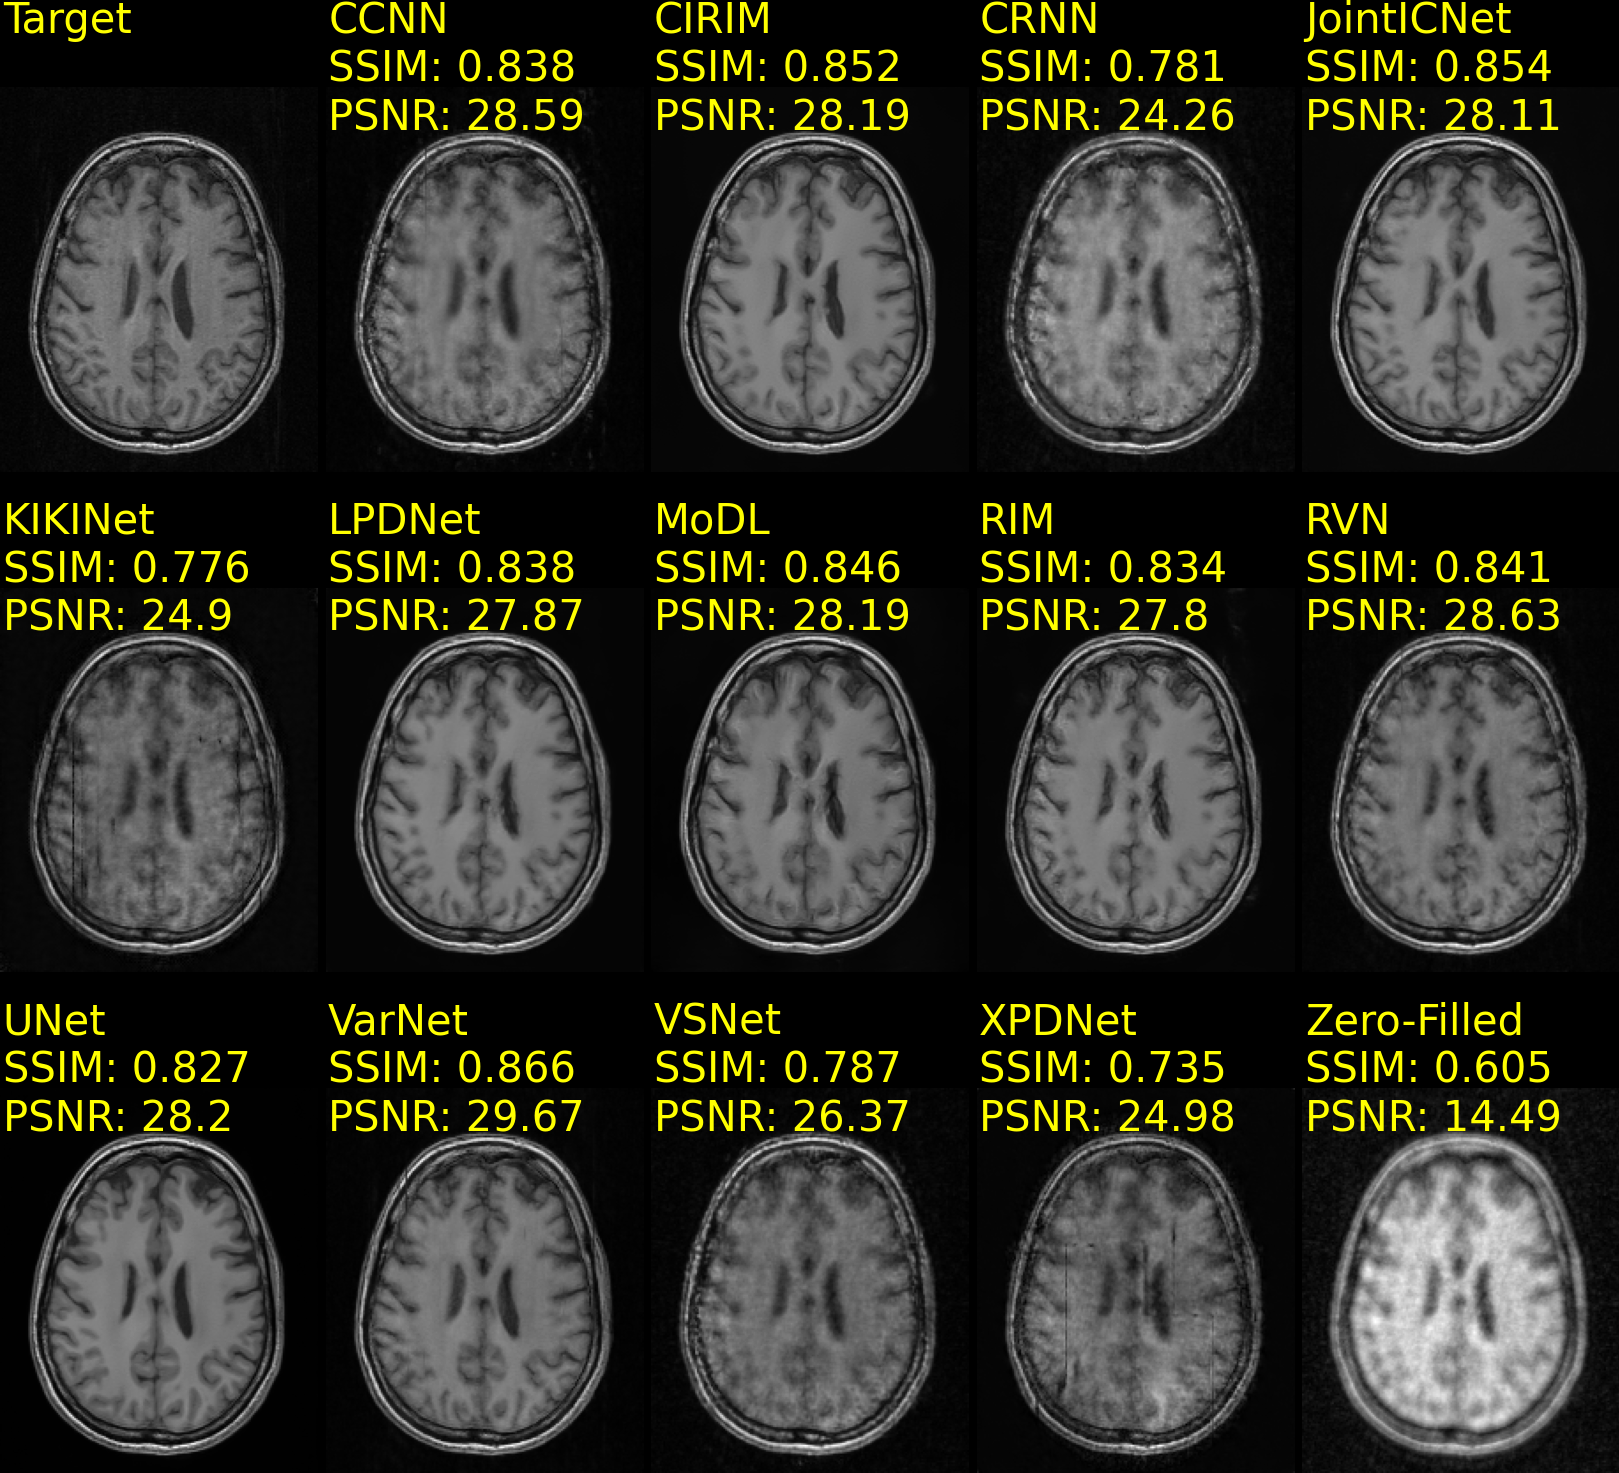

Table 2 presents the reconstruction task performance of models trained on the CC359 and fastMRIBrains datasets. The Variational Network (VarNet) achieved the highest SSIM and PSNR scores for 5x acceleration and the highest PSNR score for 10x acceleration on the CC359 dataset. The Joint Deep Model-Based MR Image and Coil Sensitivity Reconstruction Network (JointICNet) scored the highest SSIM for 10x acceleration on the CC359 dataset. In contrast, on the fastMRIBrains dataset, the Recurrent Variational Network (RVN) scored the highest SSIM and PSNR scores for 4x acceleration and the VarNet for 8x acceleration. The Cascades of Independently Recurrent Inference Machines (CIRIM) yielded the highest SSIM and PSNR scores on the StanfordKnee dataset for 12x acceleration, as presented in Table 3. Conversely, on the same dataset, the Convolutional Recurrent Neural Network (CRNN) was excluded from the analysis due to unstable gradient computation, although trained across a wide range of learning rates (104superscript10410^{-4} to 109superscript10910^{-9}).

Example reconstructions of brain data are shown in Fig. 5(a) and Fig. 5(b), from the CC359 dataset, and Fig. 6(a) and Fig. 6(b), from the fastMRIBrain dataset. Figure 7 shows example reconstructions of knee data from the StanfordKnee dataset.

Figure 5: Reconstructions of 12-coil T1-weighted data from the CC359 dataset, undersampled with a Poisson disc distribution 2D sampling pattern for 5x (Fig. 5(a)) and 10x (Fig. 5(b)) acceleration. The top row-first column shows the ground truth (Target) image. SSIM and PSNR scores are reported for each method and computed against the Target image. Methods are sorted alphabetically.

Refer to caption

(a) fastMRIBrains 14-coil data - 4x acceleration

(b) fastMRIBrains 14-coil data - 8x acceleration

Figure 6: Reconstructions of 14-coil T2-weighted data from the fastMRI Brains dataset, undersampled with an Equispaced 1D sampling pattern for 4x (Fig. 6(a)) and 8x (Fig. 6(b)) acceleration. The top row-first column shows the ground truth (Target) image. SSIM and PSNR scores are reported for each method and computed against the Target image. Methods are sorted alphabetically.